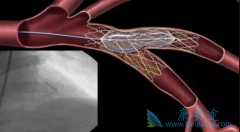

不少人都听过心脏支架手术,这种手术堪称是当代心脏病学最伟大的一项发明。你知道这个小小的支架是怎么放到心脏里去的吗? 心脏支架 是通过介入手术的方式植入到人体的,我们可以从心脏介入手术可是说起,这样更好理解。心脏介入原理其实并不复杂。 ...

为了改善冠心病介入治疗短期和长期的疗效与安全性,所以研发了支架。第一代支架是金属裸支架,使冠心病介入治疗前进了一大步,使介入治疗变得非常安全,当血管发生严重狭窄时单纯球囊扩张预处理后,再用支架把血管完全撑开,就能解除心肌缺血危险,而且 ...

心脏支架 选哪种?放最好的支架?还是放最贵的支架?今天就给大家答疑解惑!心脏支架由具有强支撑力的合金制成,不同厂家支架的金属结构略有差别。心脏支架没有植入体内之前,包裹在球囊外面。植入时给球囊加压,支架打开至预定直径,使支架与血管壁完 ...